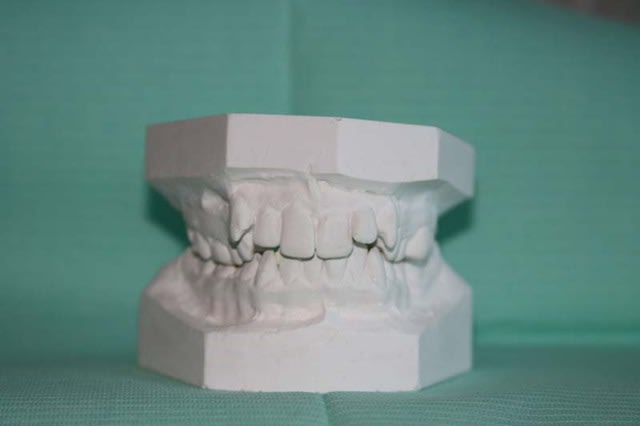

MOULAGES

Moulage 3 kvumyd - Eugenol

Moulage 1 vlrapq - Eugenol

Moulage 2 dllhb9 - Eugenol

Moulage 4 etnevt - Eugenol